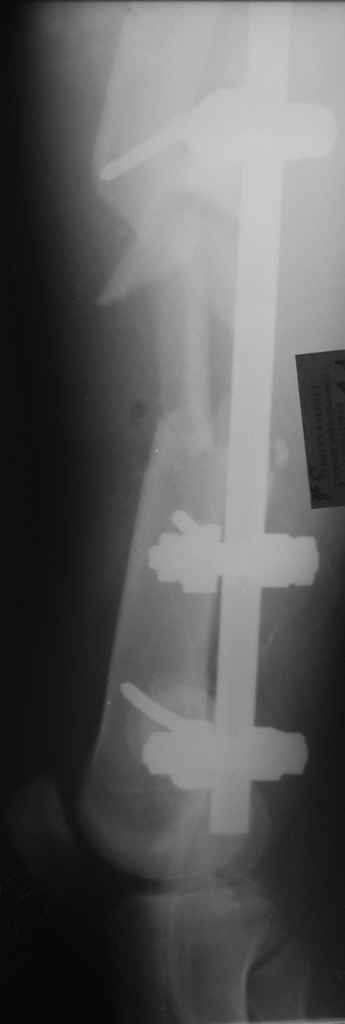

Вчера сделали снимки - положение отломков и осколков вот такое. На перевязке: из раны небольшое кол-во сгустков крови с примесью гноя , хотя бедро спокойное, гипертермии ни локальной ни общей нет. Вопрос: как быть дальше? открывать рану, "чистить" ее, наладить ее перфузию АС, АБ? что делать с осколками, попробовать перекрыть область перелома с фиксацией основных отломков аппаратом. Или осколки убрать и состыковать основные отломки с жутким укорочением и большими проблемами при зашивании раны?